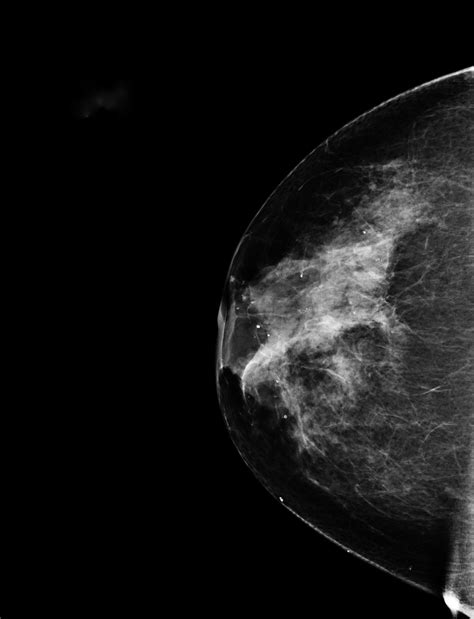

Mammakarzinom (Brustkrebs)

Das Mammakarzinom ist eine bösartige Veränderung des Drüsengewebes der Brust. Etwa jede 8. Frau in Österreich erkrankt daran. Heute geht man davon aus, dass bei der Entstehung von Brustkrebs viele verschiedene Faktoren eine Rolle spielen. Die Mehrheit aller Patientinnen mit Brustkrebs erkrankt "spontan", ohne dass in ihrer Familie bereits häufiger Brustkrebs aufgetreten wäre. Risikofaktoren können sein: das erste Kind nach dem 30. Lebensjahr.

Brustkrebs macht normalerweise weder Schmerzen noch andere typische Beschwerden, zumindest im Frühstadium. Früherkennung: regelmäßige Selbstuntersuchungen und Mammographie (ab dem 40. Lebensjahr). Besteht Verdacht auf ein Mammakarzinom, bietet eine Gewebeprobe die einzige Möglichkeit einer gesicherten Diagnose. Am häufigsten wird das Gewebe im Rahmen einer Punktion „herausgestanzt“ und histologisch untersucht. Dieser Eingriff erfolgt unter lokaler Betäubung unter Ultraschallsicht und ist für die Patientin meist nicht oder nur gering schmerzhaft. Innerhalb einer Stunde erhält man eine histologische Diagnose.

Die Brustkrebstherapie erfolgt heute sehr individuell auf jede Patientin zugeschnitten. Heute ist es bei den meisten Brustkrebs-Patientinnen möglich, bei einer Operation die Brust zu erhalten. Je nachdem, wie groß die Gefahr von Tumorabsiedelungen (Metastasen) im Körper ist, wird der Patientin zu einer zusätzlichen Therapie mit Medikamenten (Hormon-, Chemotherapie) geraten. Krebszellen können die Bestrahlungsschäden schlechter ausgleichen als gesunde Zellen und sterben ab.